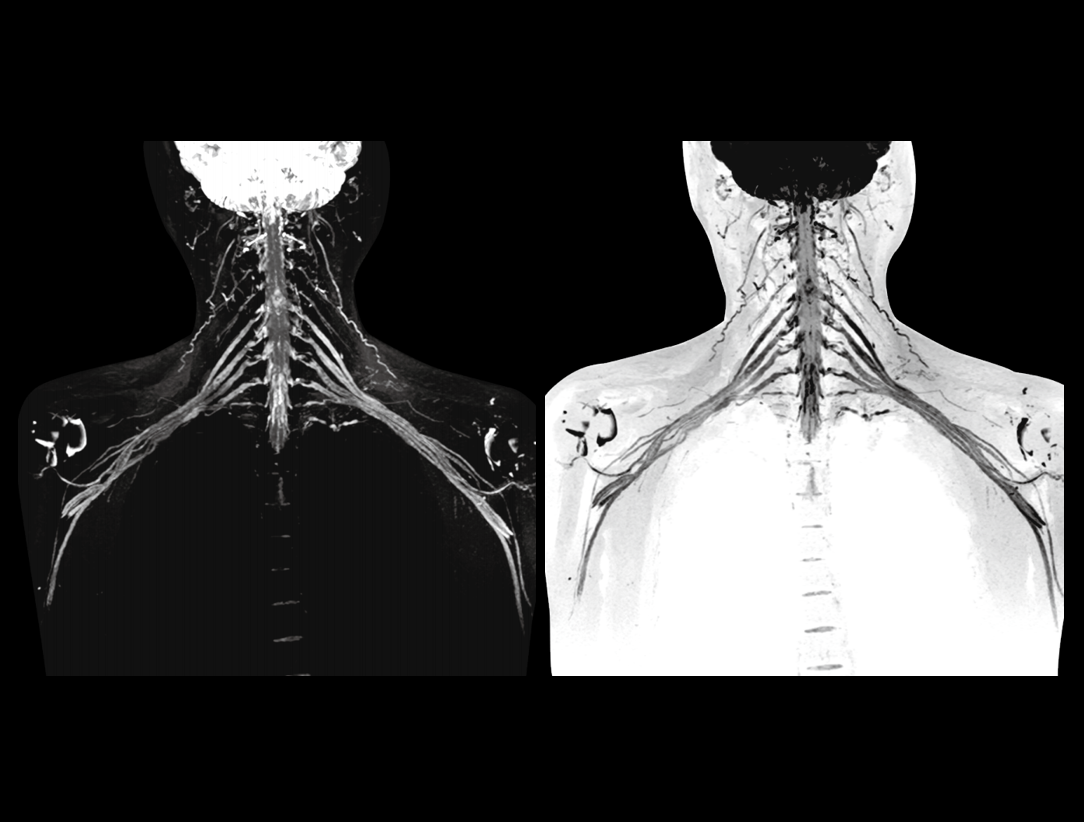

- Media